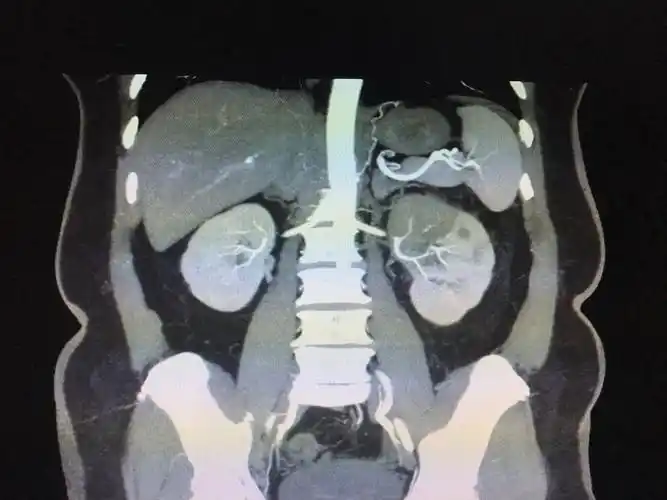

肾梗死

【病理学】肾梗死

局灶性肾梗死1例

诊断明确:肾梗死!